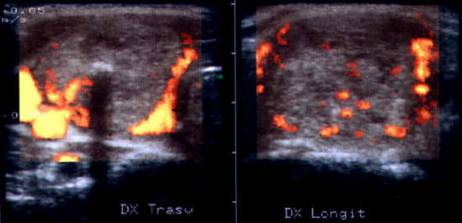

Barbat de 56 ani. Carcinom paratiroidian voluminos (44x35x41mm, 31 cc) in paratiroida inferioara dreapta.

CT – acelasi pacient:masa neomogena paratiroida dr. Cu deplasarea traheei spre stanga.